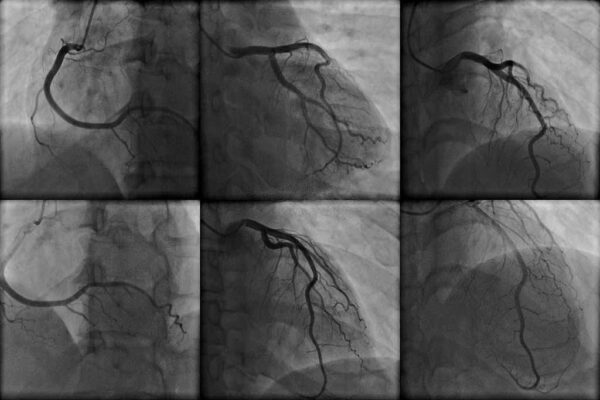

أثناء عملية قسطرة القلب سوف يتم حقن صبغة ملونة الى داخل الشرايين من خلال قسطرة (أنبوبة بلاستيكية رقيقة) بينما يقوم طبيب القلب المعالج بمتابعة تدفق الدم عبر القلب على شاشة جهاز أشعة إكس.

النتائج سوف تظهر إن كان تدفق الدم الى ومن القلب يسير بشكل طبيعي أو إن كان هناك أي انسدادات. النتائج الغير طبيعية تعني وجود انسداد في شريان أو أكثر. في حالة وجود انسداد في أحد الشرايين قد يقوم طبيب القلب المعالج باللجوء لقسطرة علاجية أثناء عملية القسطرة التشخيصية ومن الممكن أن يقوم بتثبيت دعامة شريانية لتحسين تدفق الدم بشكل فوري.